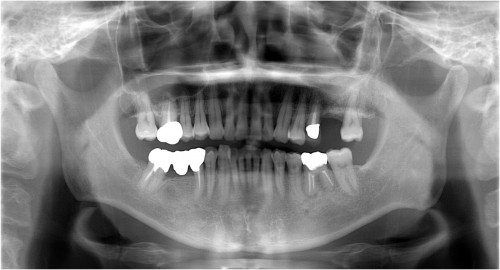

インプラント埋入直前

被せ物装着後